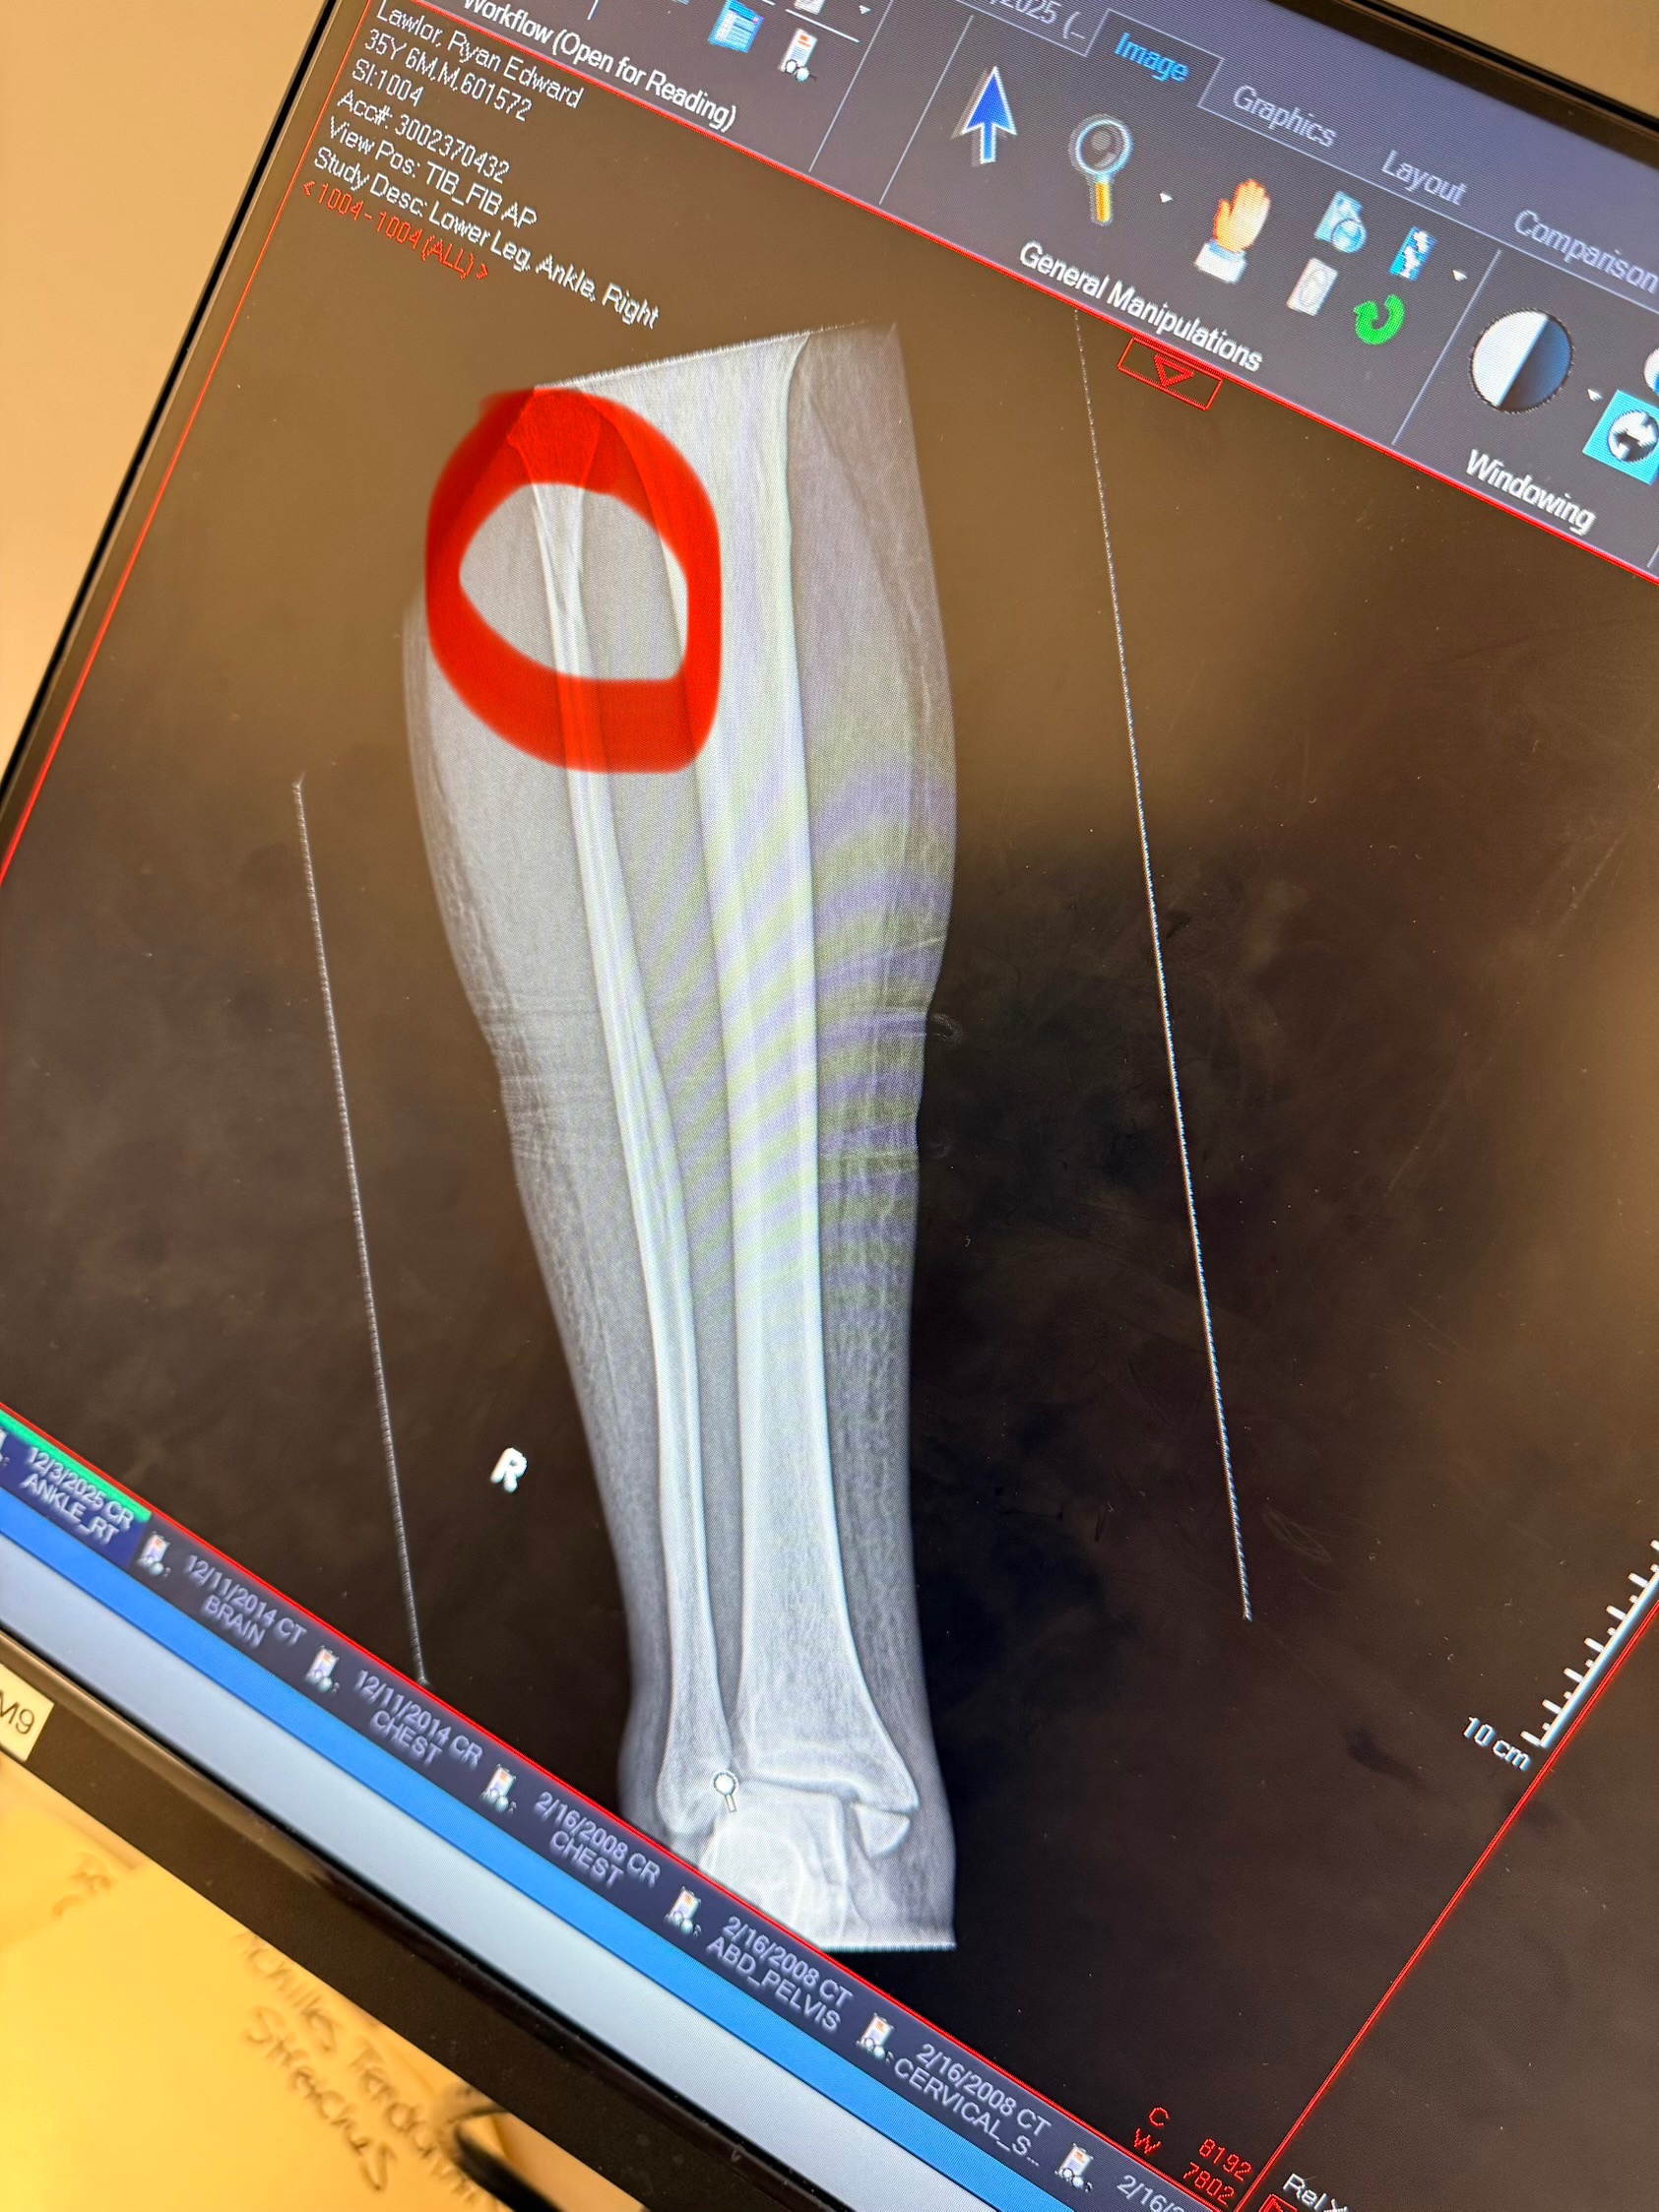

Hi, I am writing on behalf of my son. He fell and broke his tibula, fibula and tore all the tendons in his ankle. He does have health insurance to pay for this, but will be off for at least 12 weeks and does not have any short-term disability. He needs help paying his rent and monthly bills as he is a server at a downtown restaurant. He has a 3-year-old son that he also cares for. Any help that you would be able to give would be so greatly appreciated. No matter how small the donation is every bit helps.